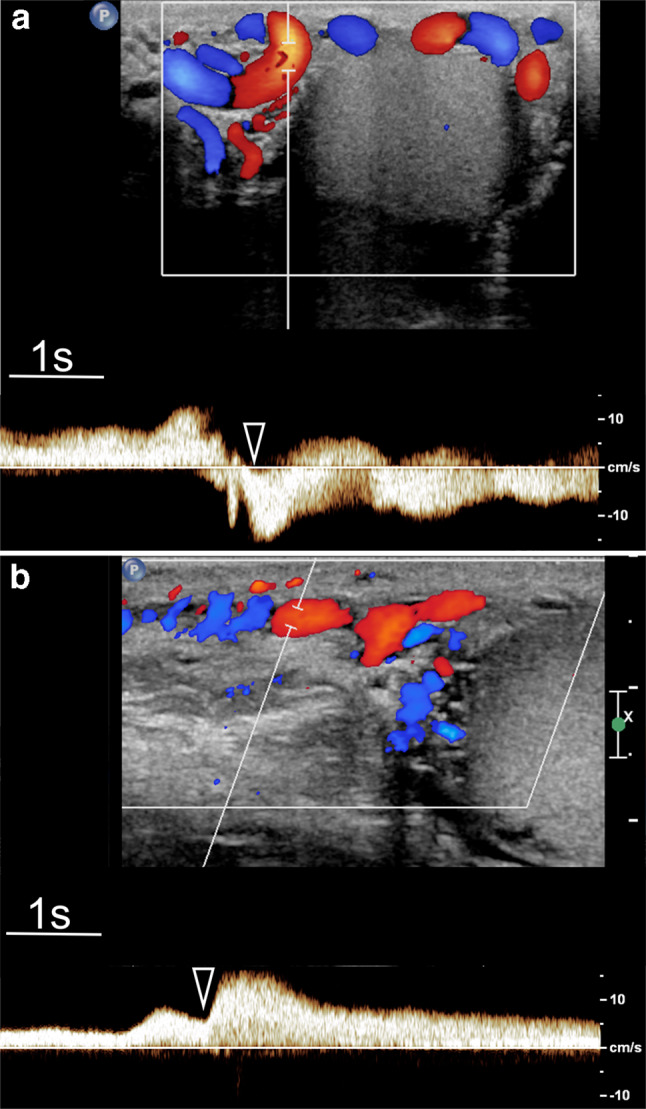

Diagnosis of reflux is obtained by combining colour Doppler interrogation and spectral analysis. The first analysis is with the colour Doppler mode, which provides a panoramic view of the spermatic vessels, their relationship with testis, information in real time about direction of flow and on how it changes in different positions and during the Valsalva manoeuvre. Use of high-end equipment with good colour Doppler sensitivity is recommended to avoid false-negative results for varicocele detection. Using high-specification equipment, reflux can often also be appreciated at grey-scale US. The examination technique is crucial. Reflux can be missed with the patient supine and it is best detected in the standing position during the Valsalva manoeuvre [62]. Colour Doppler interrogation is subjective, and findings must be substantiated with spectral Doppler analysis which allows measurement of the duration and characteristics of reflux (Fig. 2; this should be quantified [51]. Measurement of reflux peak velocity is optional and can be problematic because it requires a careful angle correction to be obtained in vessels with tortuous courses.

Fig.2.

Spectral Doppler analysis in varicocele. Changes of reflux while standing during Valsalva (arrowhead). a Flow inversion. b Flow increase showing a plateau throughout Valsalva. In both cases reflux persists for more than 2 s